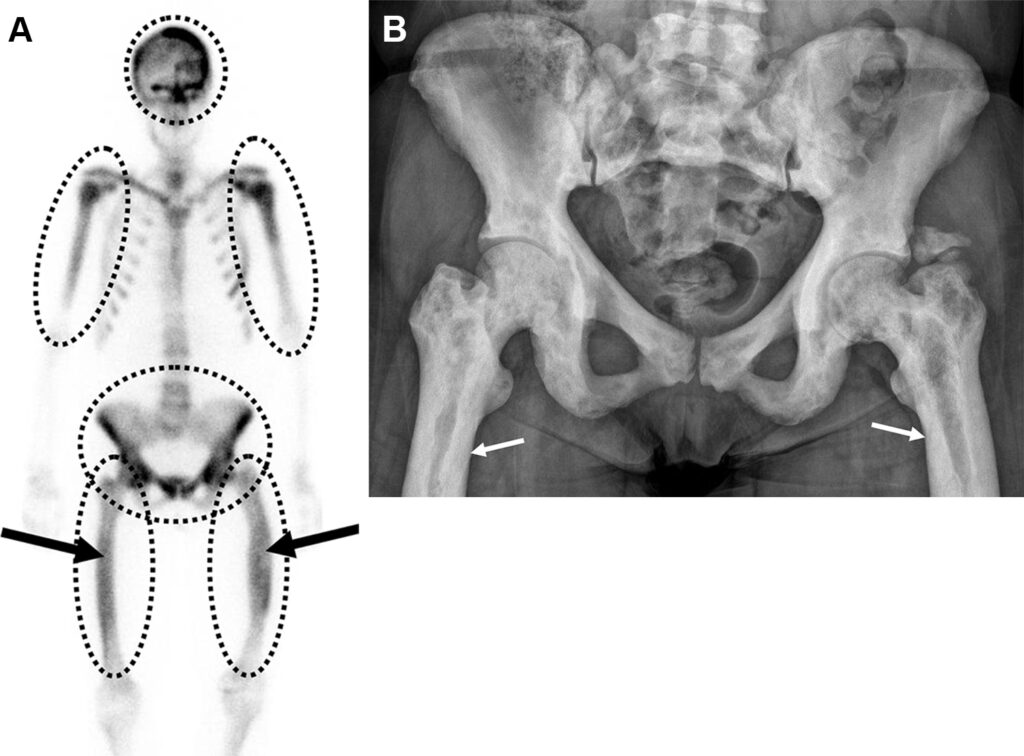

Necrosi avascolare in una donna di 22 anni con anemia falciforme e dolore osseo multifocale ricorrente.

Captazione disomogenea (“a chiazze”) a livello delle epifisi, espressione dei processi di necrosi ischemica ossea (e successiva riparazione) conseguenti alle crisi vaso-occlusive. Si evidenzia inoltre accumulo anomalo del tracciante nell’ipocondrio sinistro. Questo reperto è il segno clinico dell’autoinfarto splenico (milza funzionalmente asplenica e calcificata/sclerotica), una complicanza cronica classica dell’anemia falciforme.

La risonanza magnetica documenta il patognomonico segno della “doppia linea” (double-line sign) a carico del ginocchio nelle sequenze T2. La linea interna (iperintensa) corrisponde al tessuto di granulazione iperemico di riparazione, mentre la linea esterna (ipointensa) rappresenta il vallo di osso sclerotico che delimita la necrosi dall’osso sano.